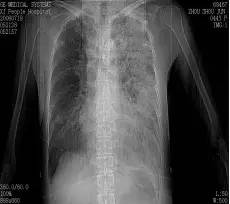

胸片

入院胸片